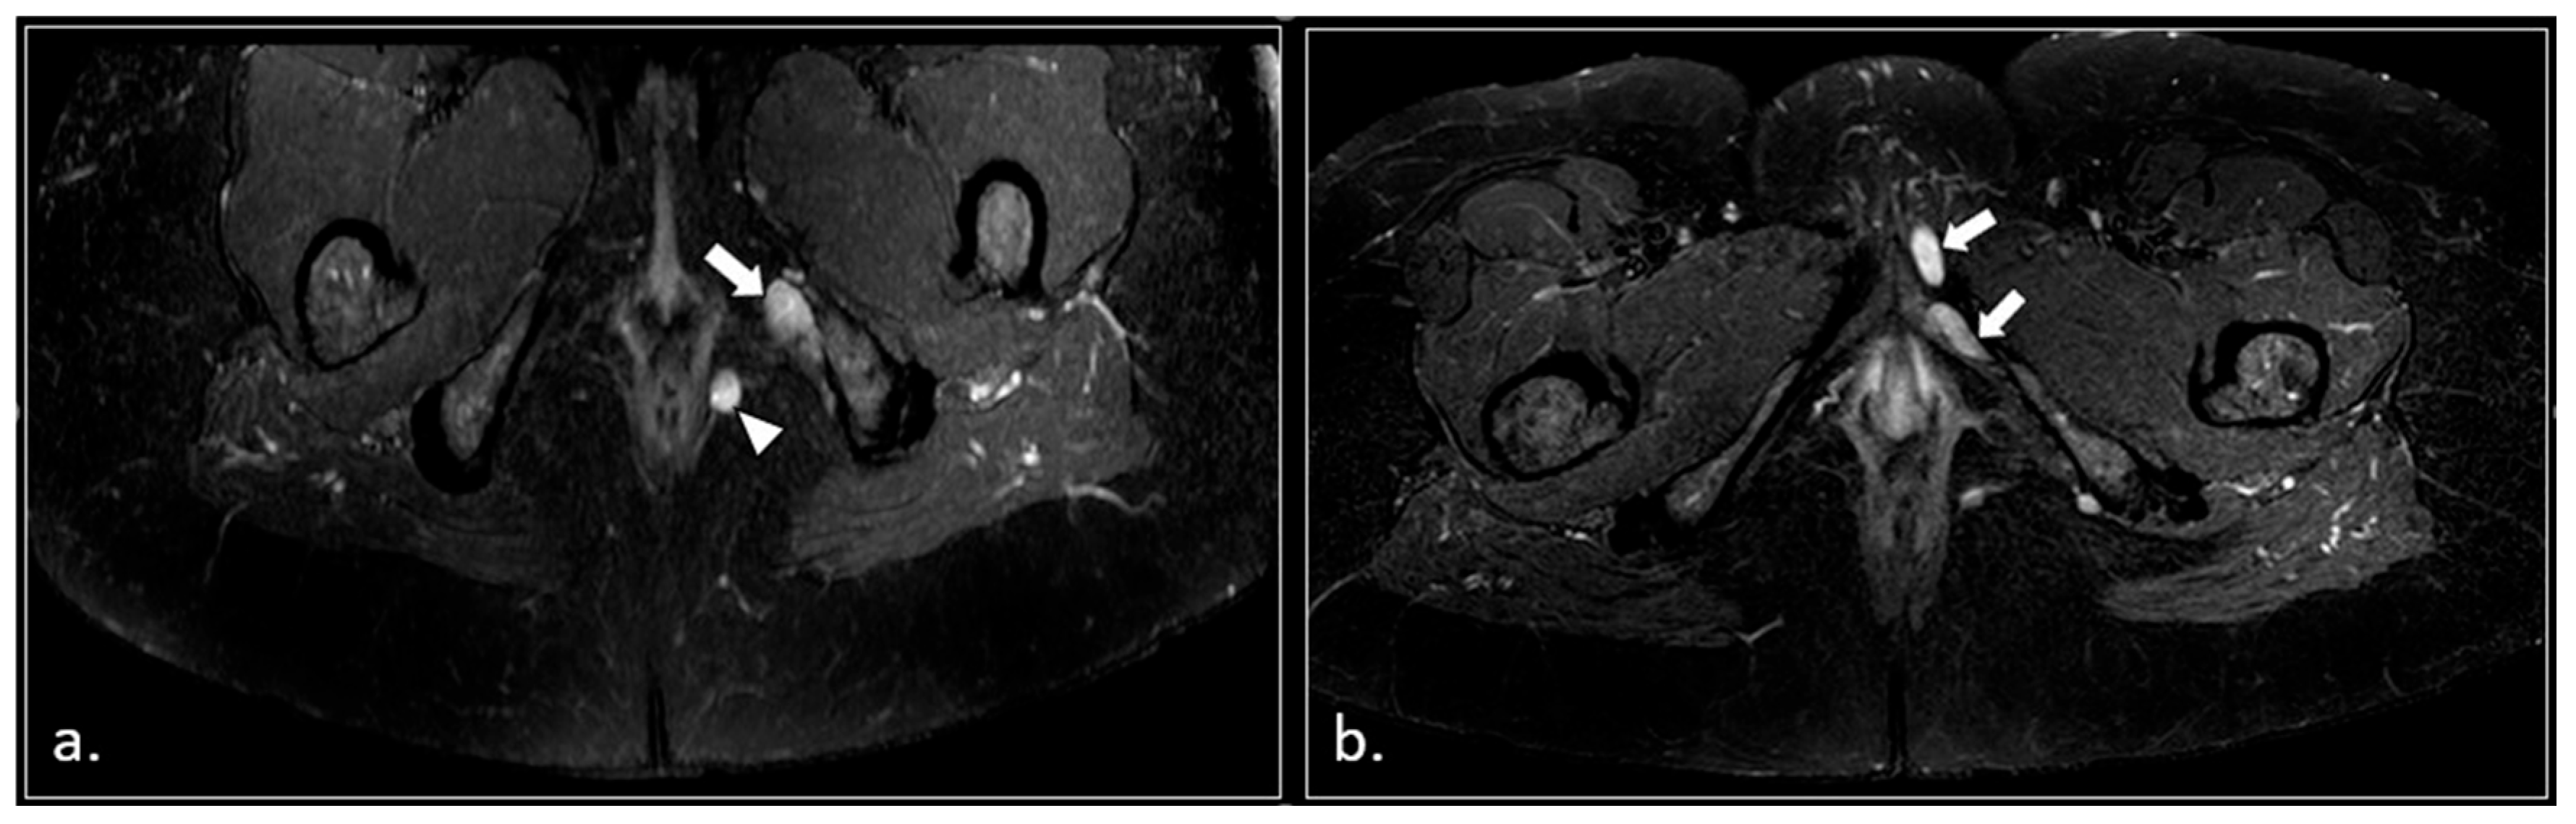

- Pudendal nerve schwannomas (2 patients);

- Varices of the pudendal vein in the Alcock canals (2 patients).